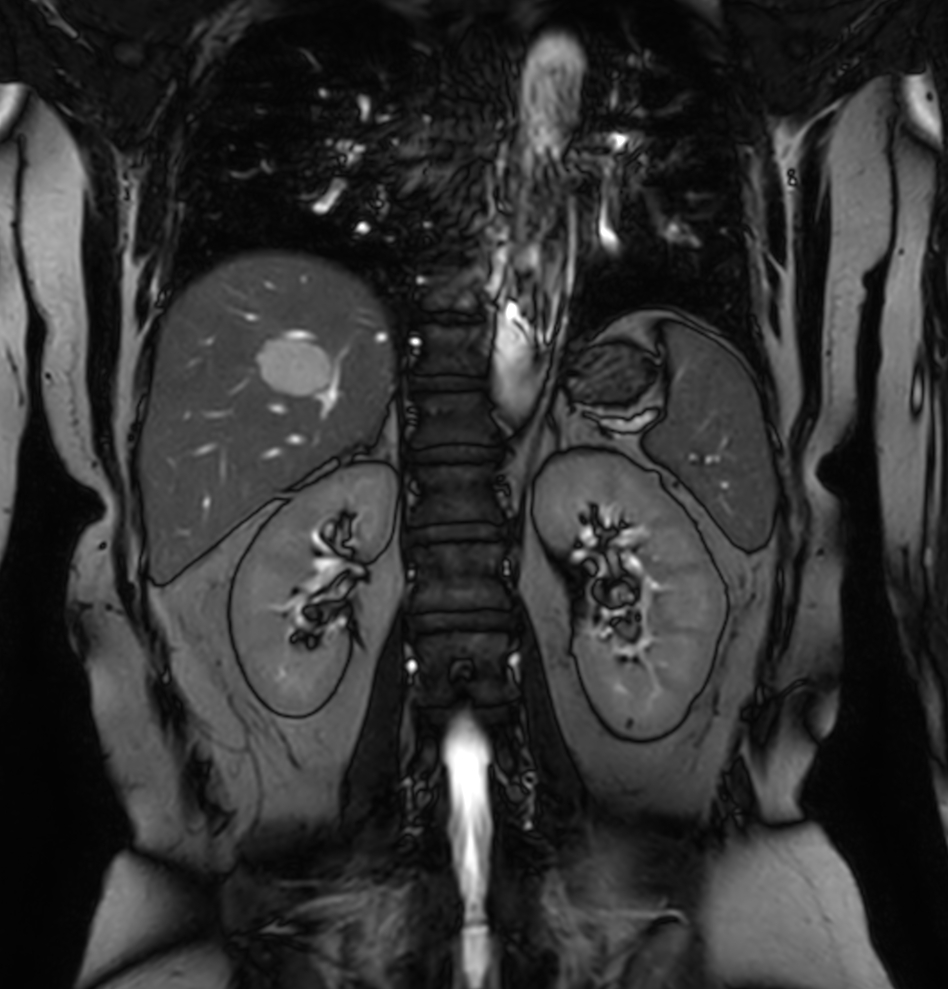

Coronal bTFE